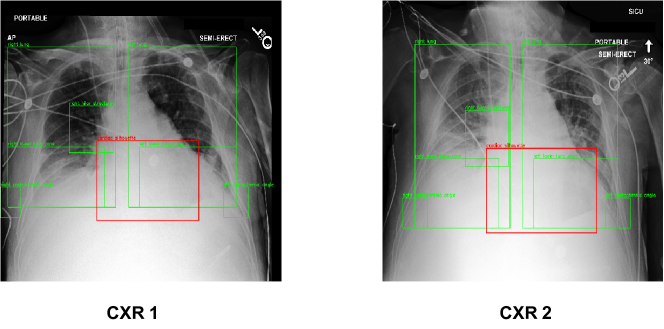

We visualize the model predictions for different pathologies. Figure 3 showcases an input image pair for the pathology label ‘Fluid Overload/ Heart Failure’ where there has been a worsening in the patient’s condition. For this particular pair, the anatomical region of interest (ROI) is ‘Cardiac Silhouette’, which is depicted with a red bounding box. Other anatomical regions that our model takes into consideration when making predictions are shown in green bounding boxes. The previous and current CXRs are named ‘CXR 1’ and ‘CXR 2’, respectively. Upon close inspection, we can see there are subtle changes within the ROI as well as in other parts of the CXR. There is increased haziness in the Left and Right Lungs, and minute changes in the Cardiac Silhouette. Similarly, Figure 4, depicts the input image pair for the pathology label ‘Pneumonia’, and the case where there has been an improvement in the patient’s condition. For this particular pair, the anatomical ROI is ‘Right Lower Lung Zone’. In addition to changes within the ROI, there are significant improvements in the regions ‘Left Mid Lung Zone’ and ‘Left Lower Lung Zone’. The Local model focuses only on the ROI, whereas the Global model focuses only on the entire image. Hence, both of these fail in making correct predictions over these images. Our CheXRelNet model builds associations between various regions and hence is able to factor in the minute changes across the entire anatomy while making predictions.

Figure 4: Qualitative results for pathology D9, class: Improved